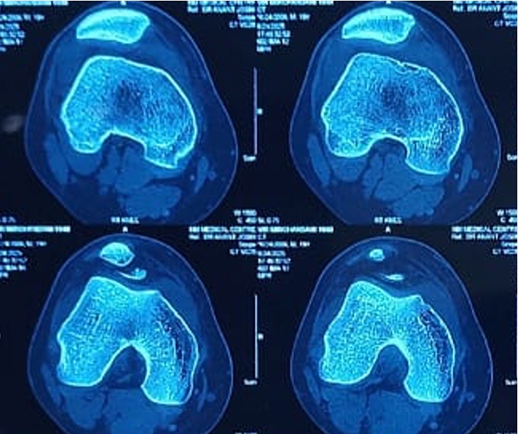

The patient was administered painkillers and ice fomentation and underwent an X-ray of his knee joint. An osteochondral fragment was visible in the knee joint, but we were not able to determine where the origin of the fragment was. A computed tomography scan of the knee joint was performed, and the fragment was identified to be originating from the distal LFC and was measuring 2.5 cm × 2.5 cm. The Insall Salvati ratio was 1.36, and the Caton Deschamps Ratio was 1.6. The Tibial Tuberosity–Trocheal Groove (TT–TG) distance was 20 mm, and his knee was a Dejour type B. A standing scannogram was not possible for the patient due to pain. The decision to avoid a tuberosity osteotomy was made as the TT-TG distance was just at the borderline with a slightly high Caton–Deschamps index. The decision to perform a lateral parapatellar arthrotomy with a strong medial patellofemoral ligament (MPFL) reconstruction was deemed sufficient to maintain patella stability. The final decision would be taken intraoperatively after tightening of the MPFL graft regarding the requirement of a tuberosity osteotomy. Fig. 2, 3.

Figure 2: Computed tomography scan of right knee – axial cuts.

Figure 3: Computed tomography scan of right knee – coronal and sagittal cuts.